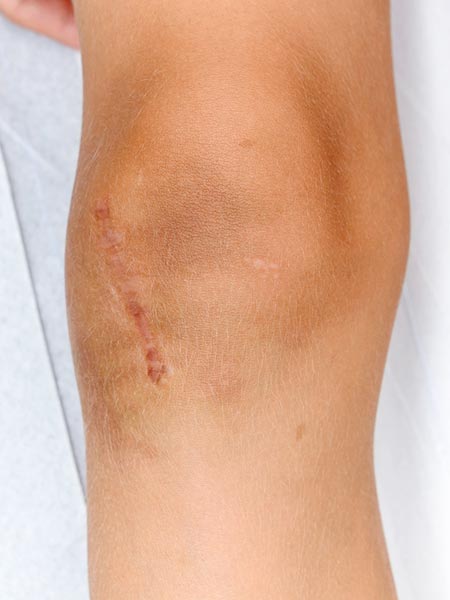

Foto des Patienten 3 Monate nach erfolgreicher Resektion des vollständig embolisierten PTEN-Hamartoms.

Das PTEN-Hamartom-Syndrom wird oft erst verzögert diagnostiziert. Wegweisend sind dabei oft mehrere arteriovenöse Malformationen (AVM), die angiographisch eher kugelig aneurysmatisch erscheinen, sowie eine deutliche begleitende, schmerzhafte Weichteilraumforderung. Wenn dazu der Kopfumfang erweitert ist, kann dem eine PTEN-Mutation zugrundeliegen. Bei der Embolisation dieser AVMs kommt es häufig zu frühen Rezidiven, eine Resektion des verschlossenen Nidus sollte angestrebt werden, wenn immer technisch möglich. Dies war auch bei diesem Patienten geplant. Das Rezidiv ereignete sich bereits früh nach der ersten, angiographisch vollständigen Embolisation. Nach erneuter Embolisation wurde der extraossäre Nidusanteil dann erfolgreich reseziert. Der intraossäre Anteil in der Tibia zeigt in der bisherigen Nachsorge kein Rezidiv.